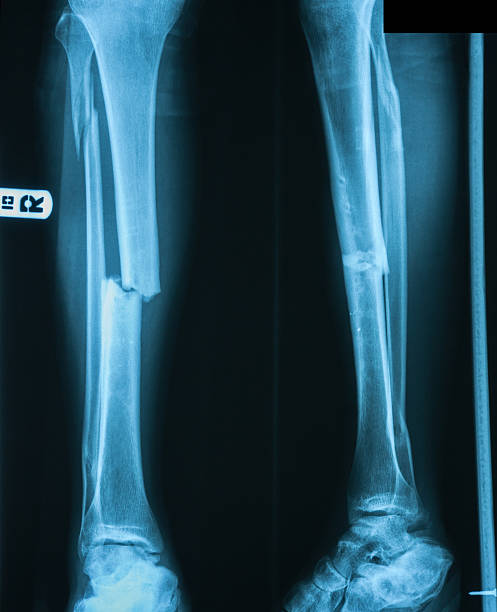

Анатомия человека: берцовая кость в деталях